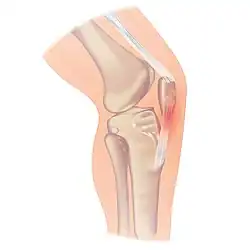

Patellar tendinitis

| Location of the pain in patellar tendinitis | |

Patellar tendinitis, also known as jumper's knee, is an overuse injury of the tendon that straightens the knee.[1] Symptoms include pain in the front of the knee.[1] Typically the pain and tenderness is at the lower part of the kneecap, though the upper part may also be affected.[2] Generally there is no pain when the person is at rest.[2] Complications may include patellar tendon rupture.[2]